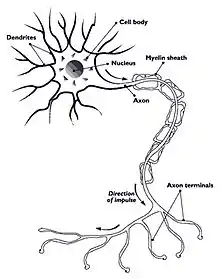

A human nerve cell is composed of various components: the soma, or cell body (which has a nucleus), the axon (by which nerve signals travel), the myelin sheath, which provides conductivity and allows electrical signals to travel through nerve cells, dendrites, which receive signals from other nerve cells, and axon terminals, which nerve cells use to communicate with each other via the release and binding of neurotransmitters.

Neurons communicate with each other using neurotransmitters, which travel across synapses (the space between axon terminals of one nerve cell and the dendrites of another nerve cell) and bind to their appropriate receptors. However, inter cellular communication between nerve cells depends on action potentials, which are voltage differences across membranes. Action potentials are initiated by the movement of charged ions, such as potassium and sodium, across the cell membrane through voltage dependent ion gates. These gates are opened by binding of neurotransmitters to post-synaptic cells. Thus, when a neurotransmitter binds and causes the voltage dependent ion gates to open, ions flow across the membrane, causing a voltage difference which results in an action potential.

These action potentials travel along the axon, and axon terminals and dendrites allow these potentials to move through various nerve cells. Action potentials function on the all or nothing principle. In other words, if a particular stimuli or neurotransmitter concentration does not reach required levels, no action potential will occur. Thus, if a mosquito lands on your hand, you may not feel it because the pressure changed caused by the mosquito landing on you is not significant enough to generate an action potential. However, the pressure of, for example, a handshake, does, and therefore generates an action potential, causing you to feel the other hand. Under the all or nothing principle, action potentials either occur or they do not- an amplitude difference is irrelevant so long as the threshold for an action potential is reached. Instead, the varying feeling you get depends on the rate, or frequency, of action potentials. In other words, if someone threw a pencil at you, it would hurt less than if someone hit you with a car not because the amplitude of the action potential is higher when you are hit by a car, but because nerves are transmitting action potentials much faster.

The myelin sheath surrounding axons is critical to the propagation of action potentials. It essentially serves to maintain conductivity; without it, action potentials would travel much more slowly (so, for example, you would not be able to feel something hit you until after several seconds). This also improves efficiency and decreases the amount of energy required for nerve signaling. Multiple sclerosis is an example of disease caused by the degradation of the myelin sheath in nerve cells. The degradation of this sheath prevents nerve cells from communicating with each other by reducing the effect and velocity of action potentials. Because many important functions depend on a healthy nervous system, such as speech, movement, coordination, sensation, and vision, the degradation of the myelin sheaths can have a debilitating effect.